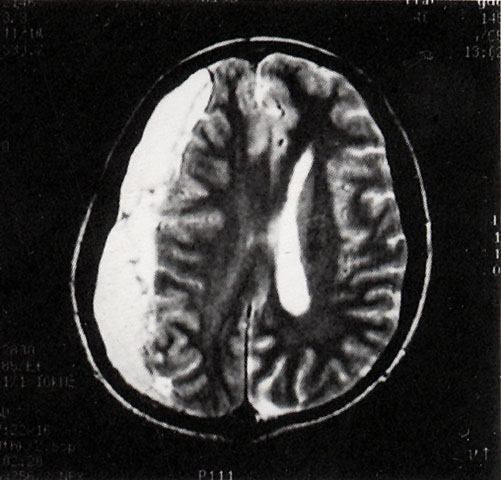

FH1036 硬膜下血肿(MRI)

图  名 硬膜下血肿(MRI)

导  学 与图1035为同一患者